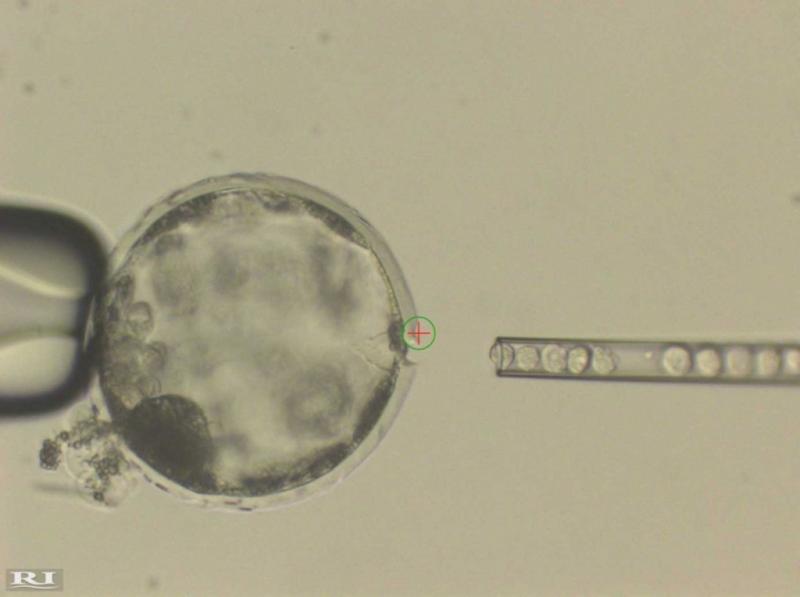

Los híbridos de humanos y animales (llamados ‘quimeras’) se crean mediante la inyección de células madre humanas en embriones de animales de días de vida, que luego se gestan en el ganado.

Modificando los genes, los científicos pueden cambiar el ADN en embriones de cerdos u ovejas de modo que sean genéticamente incapaces de formar un tejido específico, después de lo cual se añaden las células madre de una persona. La idea es que las células humanas se hagan cargo de la formación del órgano que falte, que podría ser luego utilizado en una operación de trasplante humano.